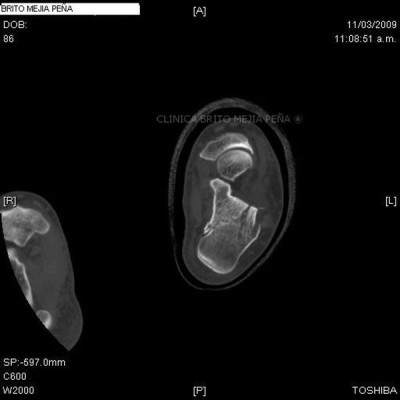

Fractura calcáneo